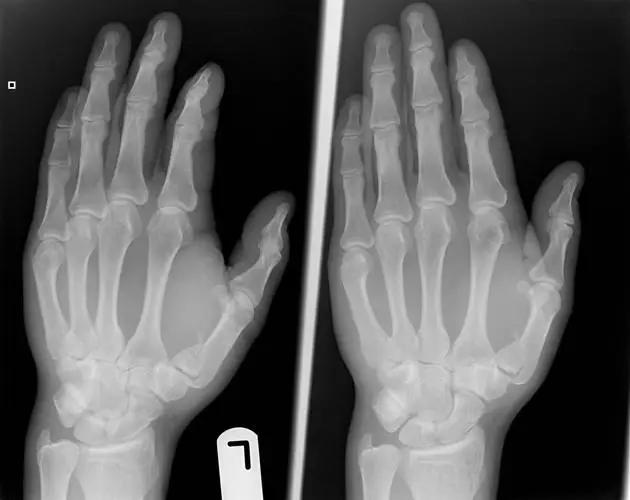

11. Buttonhole deformity/Boutonnière deformity(纽扣畸形)

伸肌腱的中央腱束断裂,使近侧指间关节突出于侧束指间,表现为近侧指间关节屈曲,远侧指间关节过伸畸形。多发生于类风湿性关节炎后畸形。

(来源:OrthoInfo- AAOS)

(来源:Medscape)